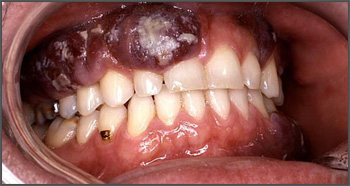

Swelling of the jaw

Swelling in the jaw is the most common symptom of osteosarcoma as a type of bone tumor that can affect the jaw. This swelling may be visible on the side of your face, but it can also occur inside your mouth. The roof of your mouth may be swollen as well, or you may notice swelling beneath your teeth depending on the location of the tumor. This inflammation is caused by the growth of the tumor inside the bone, and if it leads to gum irritation, your dentist may recommend using a toothbrush with extra-soft bristles.

Tooth mobility

Tumors in the jawbone can also lead to unexplained tooth mobility. If you notice that your teeth are loose or suddenly shifting positions, don't hesitate to let your dentist know. Tooth mobility could be caused by a tumor on your jawbone that is pushing your teeth out of place.